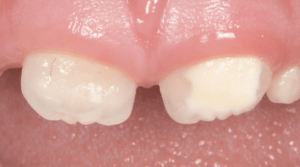

Le congrès de l’EAPD (Académie Européenne d’Odontologie Pédiatrique) a défini des critères de diagnostic en 2003. A savoir des opacités délimités, des fractures post-éruptives, des restaurations atypiques ainsi que que des extractions des molaires. (3) Le diagnostic différentiel doit surtout s’établir entre des amélogénèses imparfaites et des hypominéralisations d’origine traumatique pour les dents antérieures. Cliniquement, les dents vont présenter des colorations blanches ou brunes opaques sur une partie ou sur toute la surface de la dent (Figures 1-2-3-4).

formation dentaire pédodontie Figure 3.

Figures 1-2 : Incisives centrales atteintes de MIH

Figure 3-4 : Molaires atteintes de MIH (HSPM + MIH pour la figure 3)